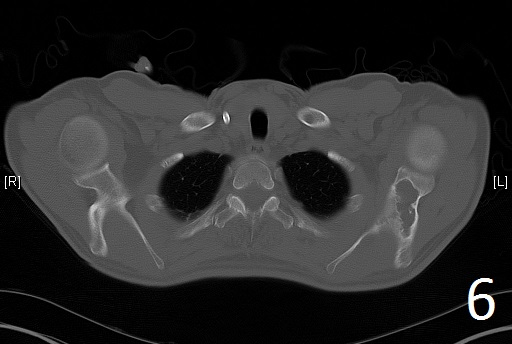

CT

• Useful to determine the extent of the lesion as well as ground glass appearance (Fig. 2-3)

Fig. 6

Fig. 7

Fig. 6-7. Axial CT reconstruction of the chest showing lytic and expansile lesion of the left scapula and ribs (polyostotic fibrous dysplasia).